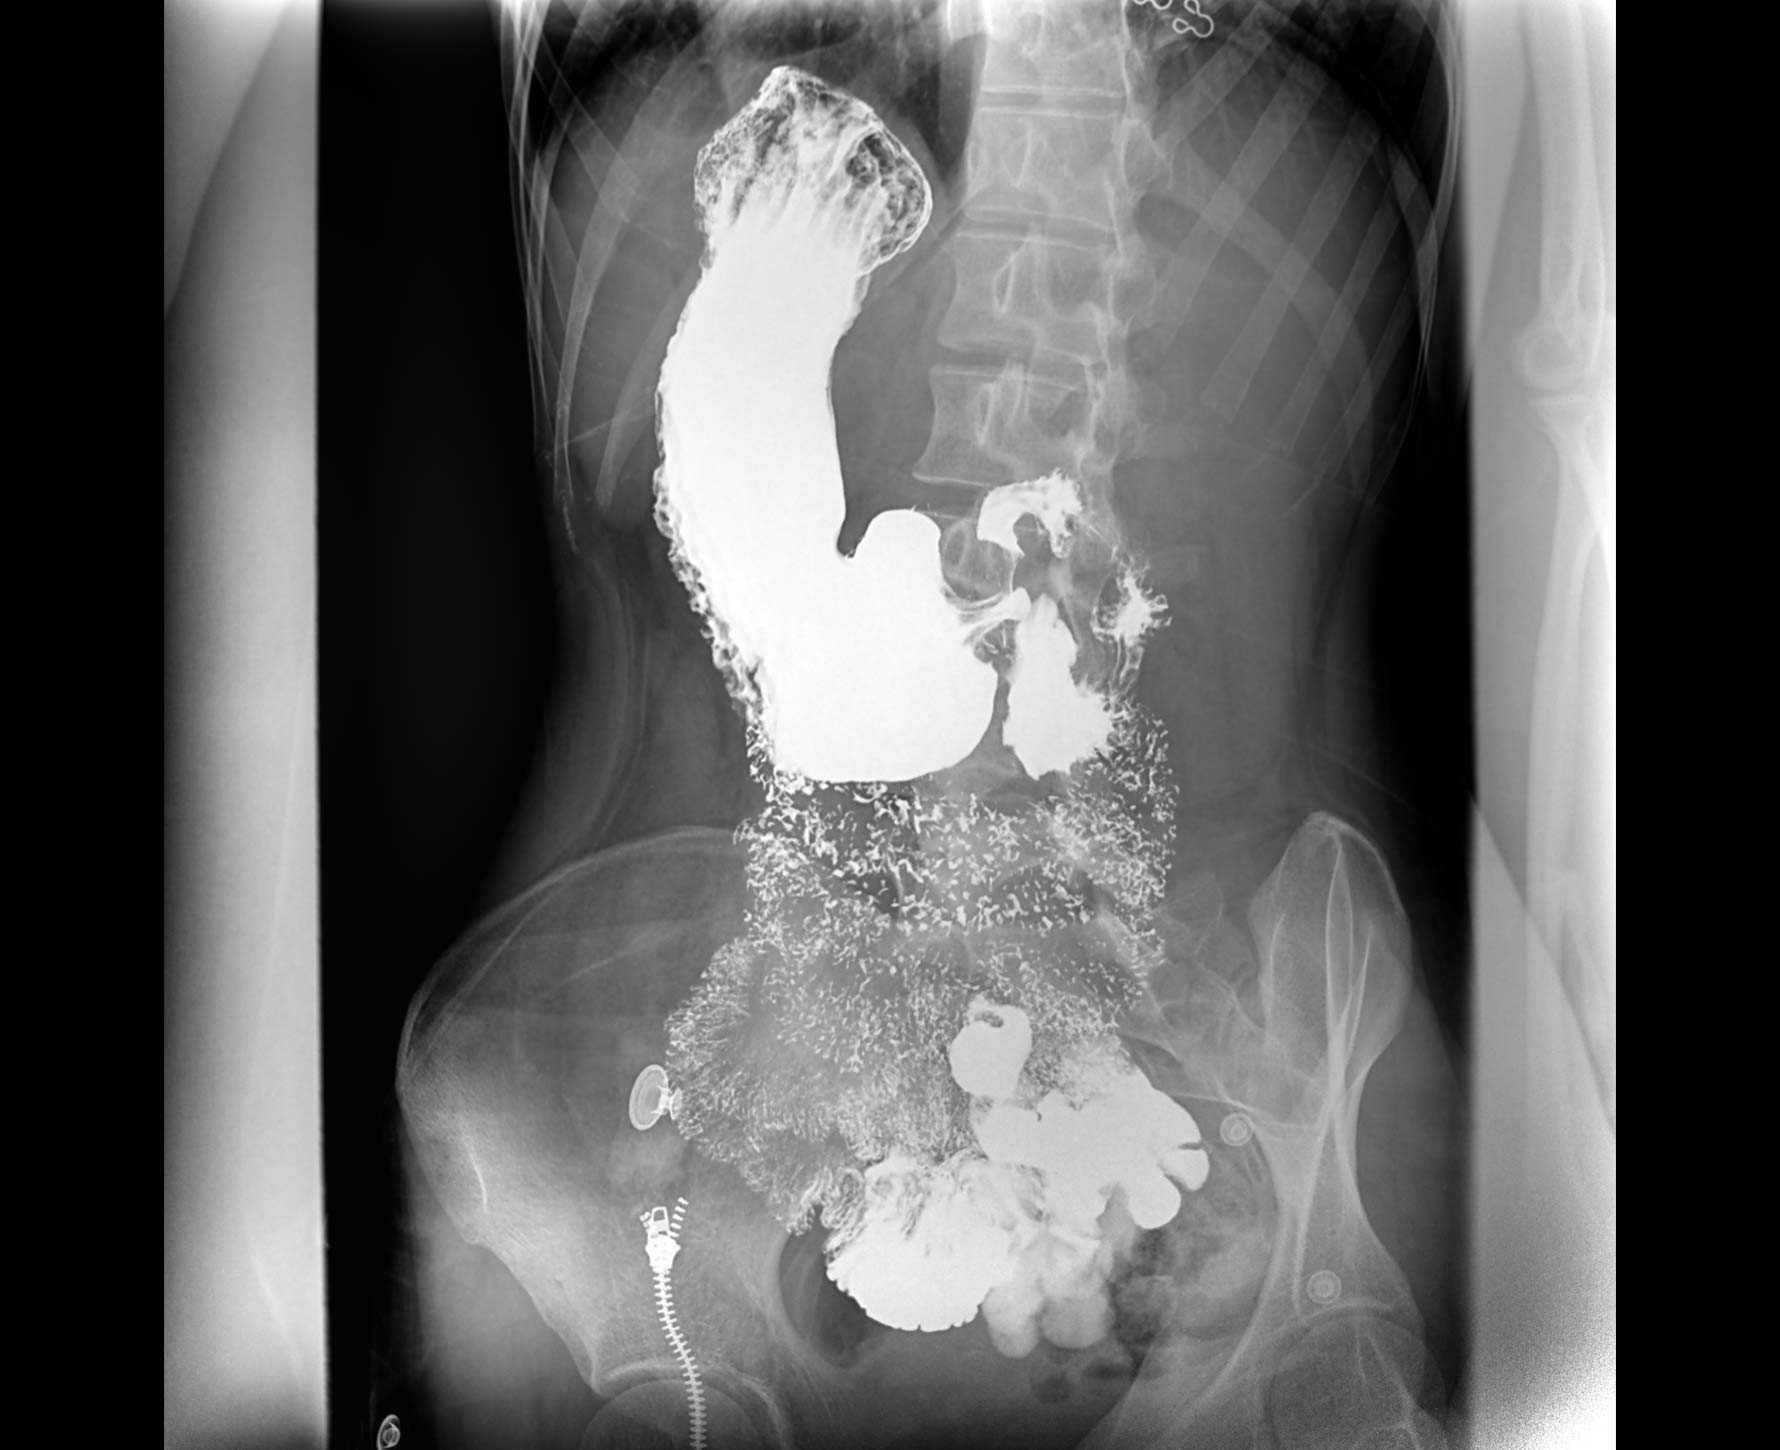

• 造影

适用于各种普通

及特殊胃肠造影检查

对胃肠造影检查影像实时保存,多次回放以便确定病灶部位,患者确诊好帮手,减少漏诊。

临床图像